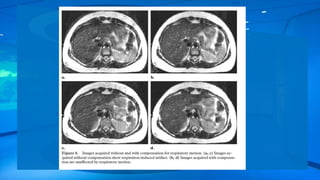

Another way to effectively reduce respiratory motion artifacts is to use

respiratory compensation or phase reordering (also called respiratory-

ordered phase encoding, or ROPE), whereby the phase encoding steps

are ordered on the basis of the phase of the respiratory cycle .

This technique allows a smooth phase variation across k-space , and

the limitation of variation to a single cycle of respiration instead of

several cycles.

Respiratory-ordered phase encoding works well in patients with regular respiratory

cycles but not in those with irregular breathing.

Respiratory gating maywork better to resolve respiratory motion artifacts , with image acquisition performed at a certain phase of the respiratory cycle. The drawback of respiratory gating is that the acquisition time is increased. Another way to effectively reduce respiratory motion artifacts is to use respiratory compensation or phase reordering (also called respiratory- ordered phase encoding, or ROPE), whereby the phase encoding steps are ordered on the basis of the phase of the respiratory cycle . This technique allows a smooth phase variation across k-space , and the limitation of variation to a single cycle of respiration instead of several cycles.

Respiratory-ordered phase encodingworks well in patients with regular respiratory cycles but not in those with irregular breathing. Real-time navigator echo gating is an elegant non–breath-hold technique that can be used to compensate for several different types of motion .